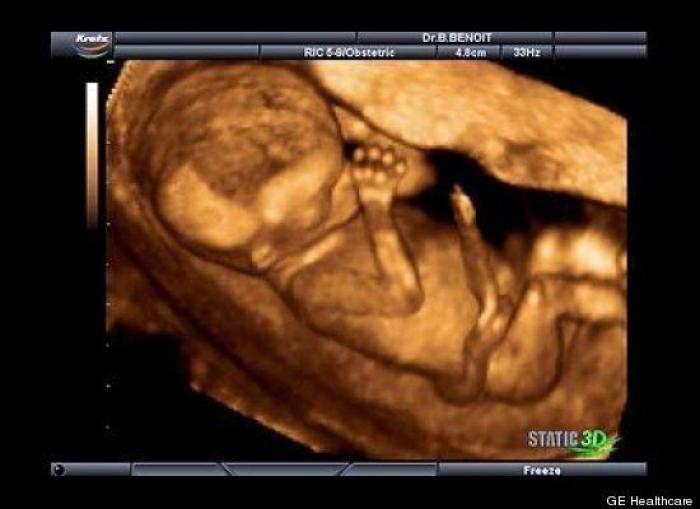

En esta galería puedes ver en fotos como es el desarrollo de un feto de semana en semana:

Desarrollo del feto, en fotos